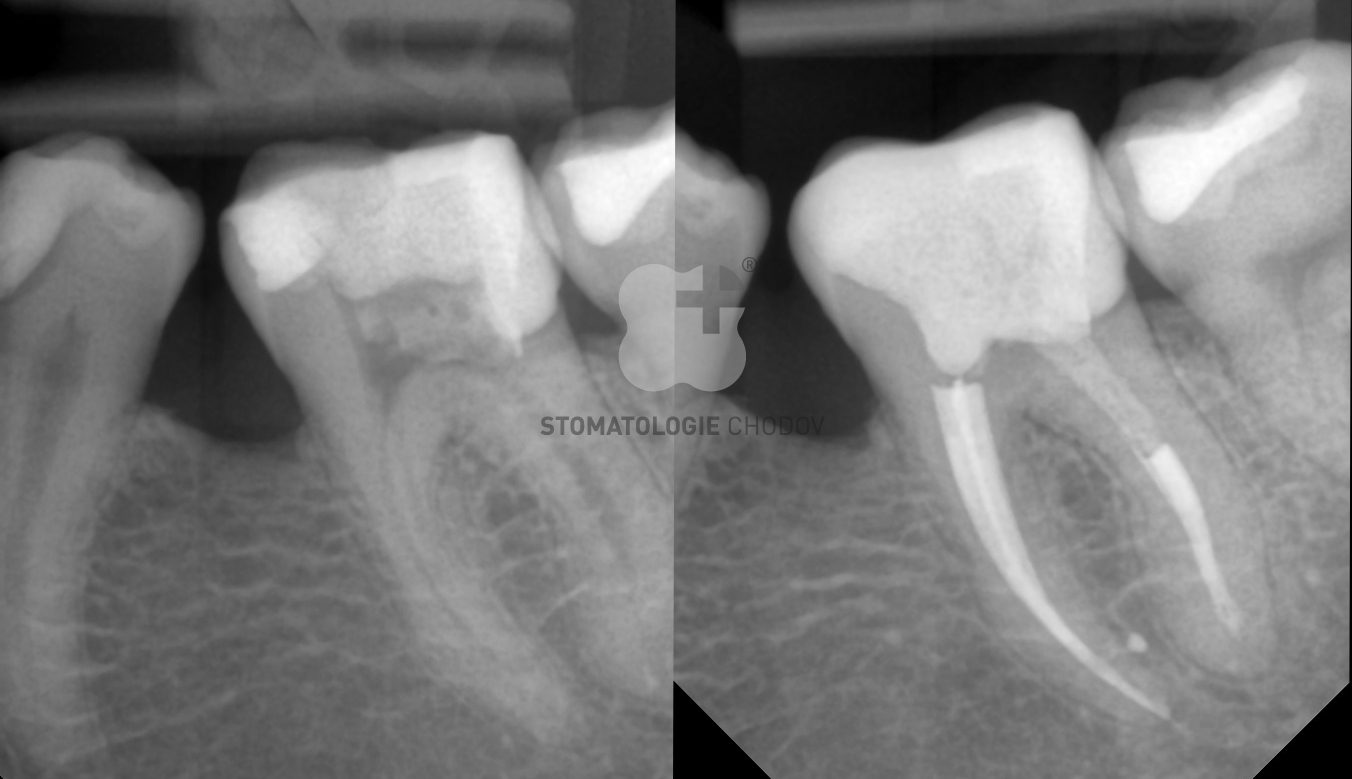

Endodontické ošetření

Mezi časté komplikace zubního kazu se řadí zánět dřeně (pulpitida) a rozšíření infekce kořenovým kanálkem až do kostního lůžka zubu (periodontitis). V některých případech mohou být zastiženy i další tkáně v dutině ústní.

Pokud taková situace nastane, je nutné provést endodontické ošetření (vyšetření a ošetření systému kořenových kanálků), během kterého probíhá opracování, čištění, dezinfekce a následné hermetické zaplnění kořenového kanálku.

Při ošetření systému kořenových kanálků v klinice používáme nejmodernější technologie:

• Bezbolestné ošetření díky lokálnímu znecitlivění;

• Dentální mikroskop s integrovanou kamerou CJ-Optik Flexion Advanced (Germany);

• Lupový systém Carl Zeiss (Eye Mag PRO S);

• Apexlokátor - elektronický přístroj pro měření délky kořenového kanálku;

• X-Smart iQ – nejnovější generace bezdrátového endomotoru s rotačním či recipročním pohybem, který umožňuje strojové opracování kořenových kanálků;

• Rubber dam (kofferdam) – zajištění čistého a nekontaminovaného operačního pole v dutině ústní;

• Intraorální digitální RTG senzor;

• Nástroje na jedno použití.